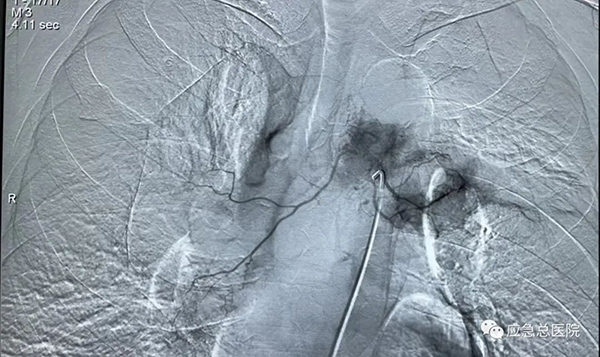

(3)经血管介入技术:常规开展支气管动脉灌注化疗、支气管动脉栓塞及血管内支架技术,应用于肺癌及咯血患者治疗,疗效确切。

应急总医院对于肿瘤引起的气道狭窄患者建立了多学科、多专业、一站式24小时急诊绿色通道,从急诊入院、接诊、检查、手术、会诊、ICU观察、复诊、回访等各个环节都形成了一整套规范化、系统化的诊治流程,使得各种情况引起的气道狭窄患者在第一时间得到最及时、最科学、最有效的镜下手术治疗。

气管镜下支架置入手术可以用于食道癌、肺癌、甲状腺癌等各种肿瘤引起的气道狭窄;其他疾病所致的气管、支气管瘘等良性气道狭窄。可以有效缓解患者气急、胸闷等呼吸困难症状,从而提高患者的生活质量,并为后续治疗提供宝贵机会。与外科手术相比,气管镜下支架置入技术具有不开刀、创伤小、操作简便、安全性高、术后恢复快、并发症少等显著优点。对于无法手术及无法耐受手术的恶性肿瘤患者,该方法创伤小,出血少,病人耐受性较好,可缓解症状,达到姑息治疗的目的。